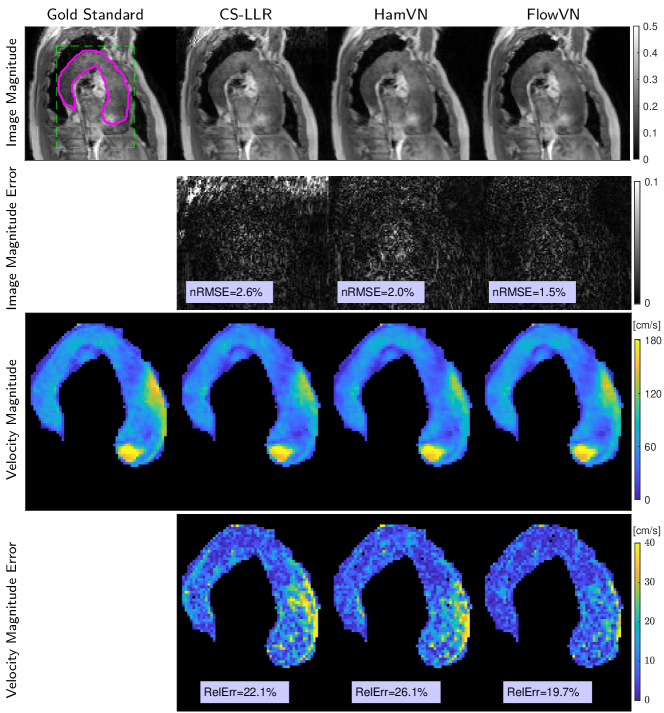

Reconstructed image magnitudes (for a single velocity encoding component), estimated velocity magnitudes and their errors of a healthy volunteer data for acceleration factor R𝑅R=14 are illustrated in Fig. 3 for retrospectively undersampled data. Compared to CS-LLR and HamVN, the proposed FlowVN provides better reconstruction accuracy in terms of image magnitude and velocities. Scatter plot and correlation analysis further suggest that the velocity magnitude image estimated via FlowVN is in better agreement with ground truth. As shown in Supplementary Table 2 these observations extend to other acceleration factors R𝑅R (6–22) as tested on 7 healthy volunteers.

Refer to caption

Figure 3: Reconstruction results on retrospectively undersampled data. Image magnitudes and estimated 4D velocity magnitude maps on retrospectively 14×\times undersampled data from a healthy volunteer. Corresponding slice locations are illustrated with red dashed lines, indicating crossection of the aorta and systolic peak. Scatter plot of velocity magnitude over manually segmented aorta (contour shown in magenta) is given together with correlation analysis (y=ax+b𝑦𝑎𝑥𝑏y=ax+b).

Figure 4: Retrospective reconstruction of the data from patient with abnormal flow pattern. Reconstruction results of 10×\times retrospectively undersampled patient data shown at systolic peak flow. Manual aorta segmentation and field-of-view are shown with magenta and green dashed lines, respectively.